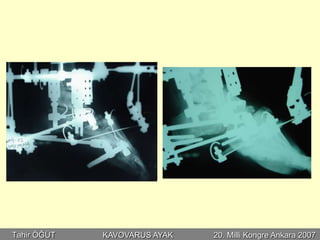

•Perkütan aşiloplasti

•Plantar fasya gevşetme

•Peroneus longus transferi

•Kalkaneal osteotomi

•1. Metatars osteotomisi

Postop 3. ay